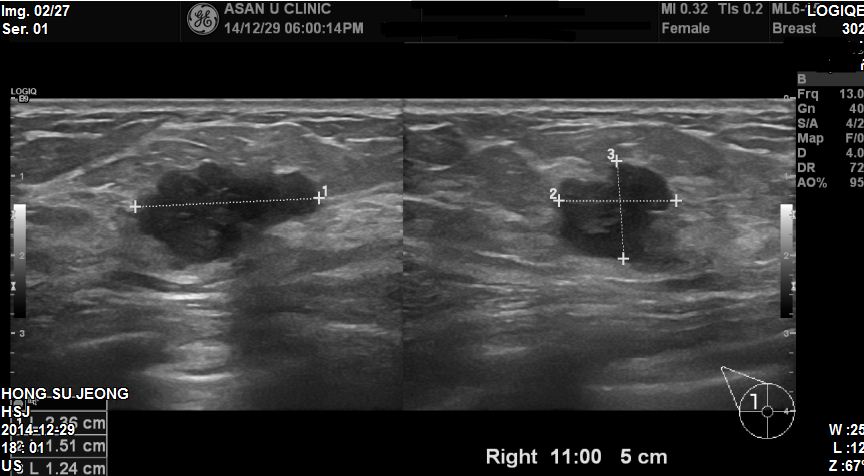

양측유방에 만져지는 혹으로 내원하신 40세 여자환자분이십니다

유방초음파와 중심핵생검으로 침윤성 유방암이 진단되셨습니다.